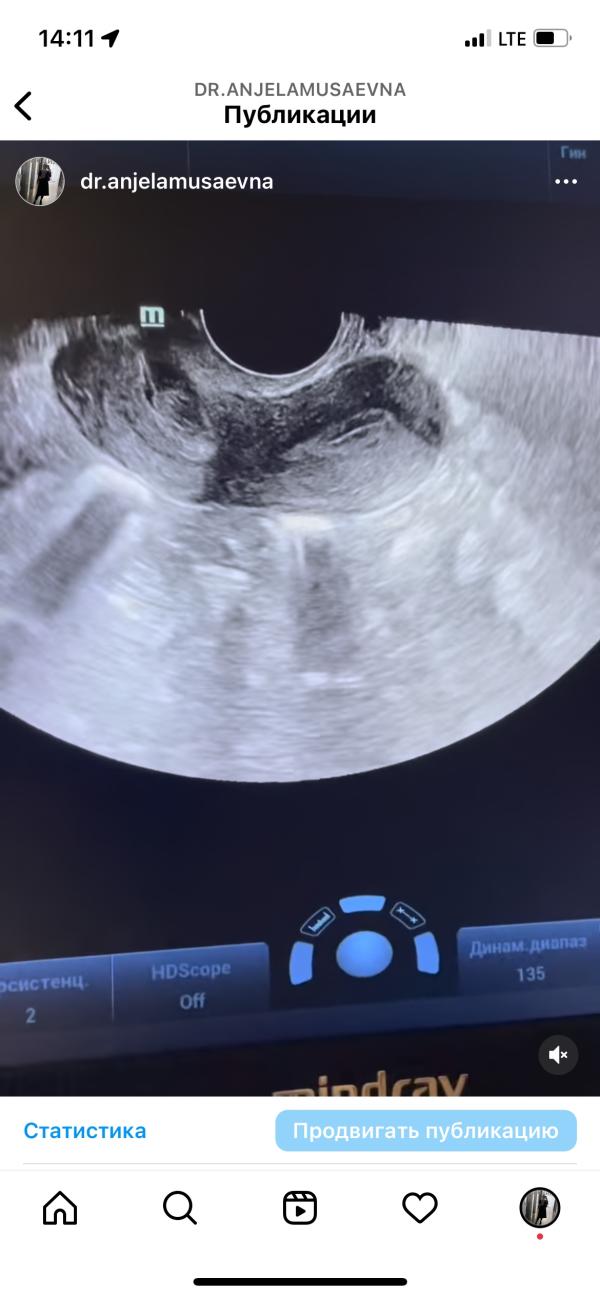

Инфантильная матка: что это такое, причины, симптомы, диагностика и лечение гипоплазии

Инфантильность (гипоплазия) матки .